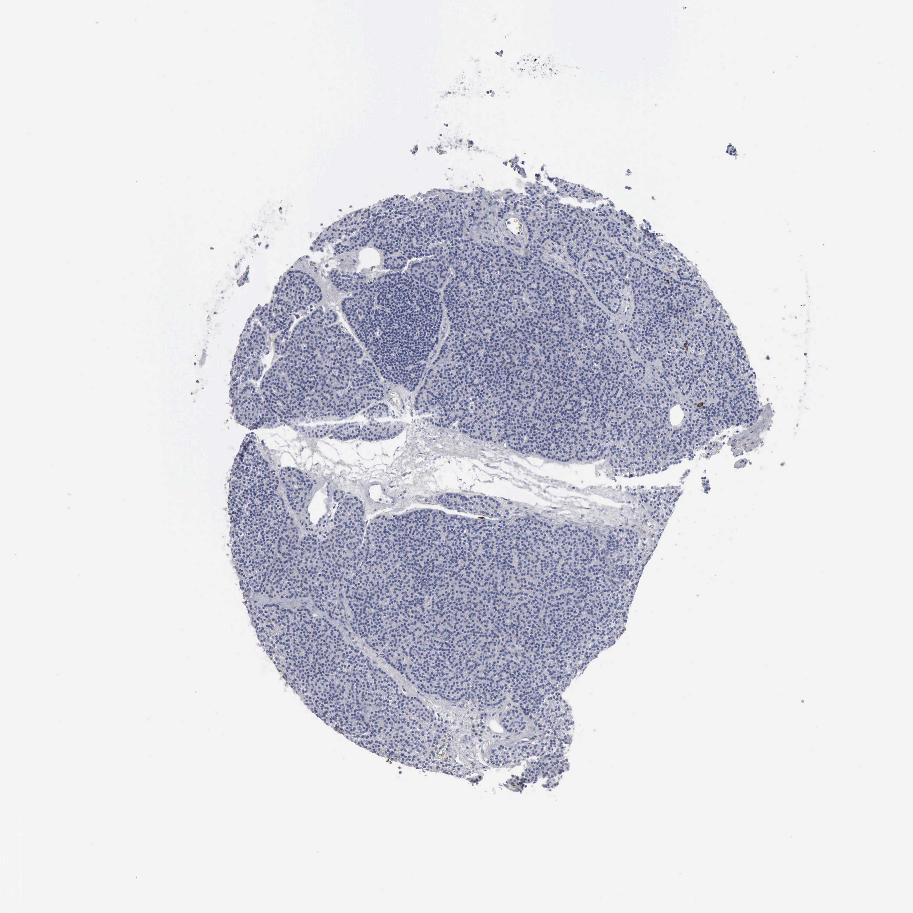

TISSUE PRIMARY DATA PARATHYROID GLAND Show tissue menu

PARATHYROID GLAND - Antibody stainingi

Antibody staining in the annotated cell types in the current human tissue is reported as not detected, low, medium, or high, based on conventional immunohistochemistry profiling in selected tissues. This score is based on the combination of the staining intensity and fraction of stained cells.

Each image is clickable and will lead to virtual microscopy that enables deeper exploration of all samples and also displays staining intensity scores, fraction scores and subcellular localization as well as patient and tissue information for each sample.

Antibody HPA052634Antibody CAB000363

Glandular cells Not detectedNot detected